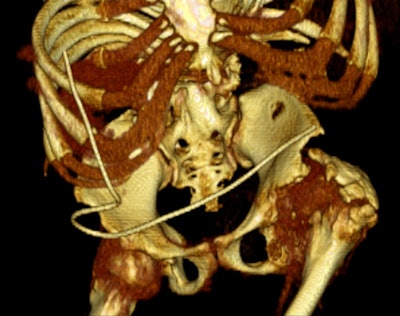

An 18-year-old female with "after-party amnesia" presented with severe stomach pain and bruises to the head. An investigation showed vaginal bleeding was from the bladder. Full-scale emergency room investigation showed severe left kidney fracture and contusion, but intact vessels and ureter. Three-month follow-up renography shows 28% kidney function on left side as the only sequelae. Image courtesy of Dr. Vibeke Logager.